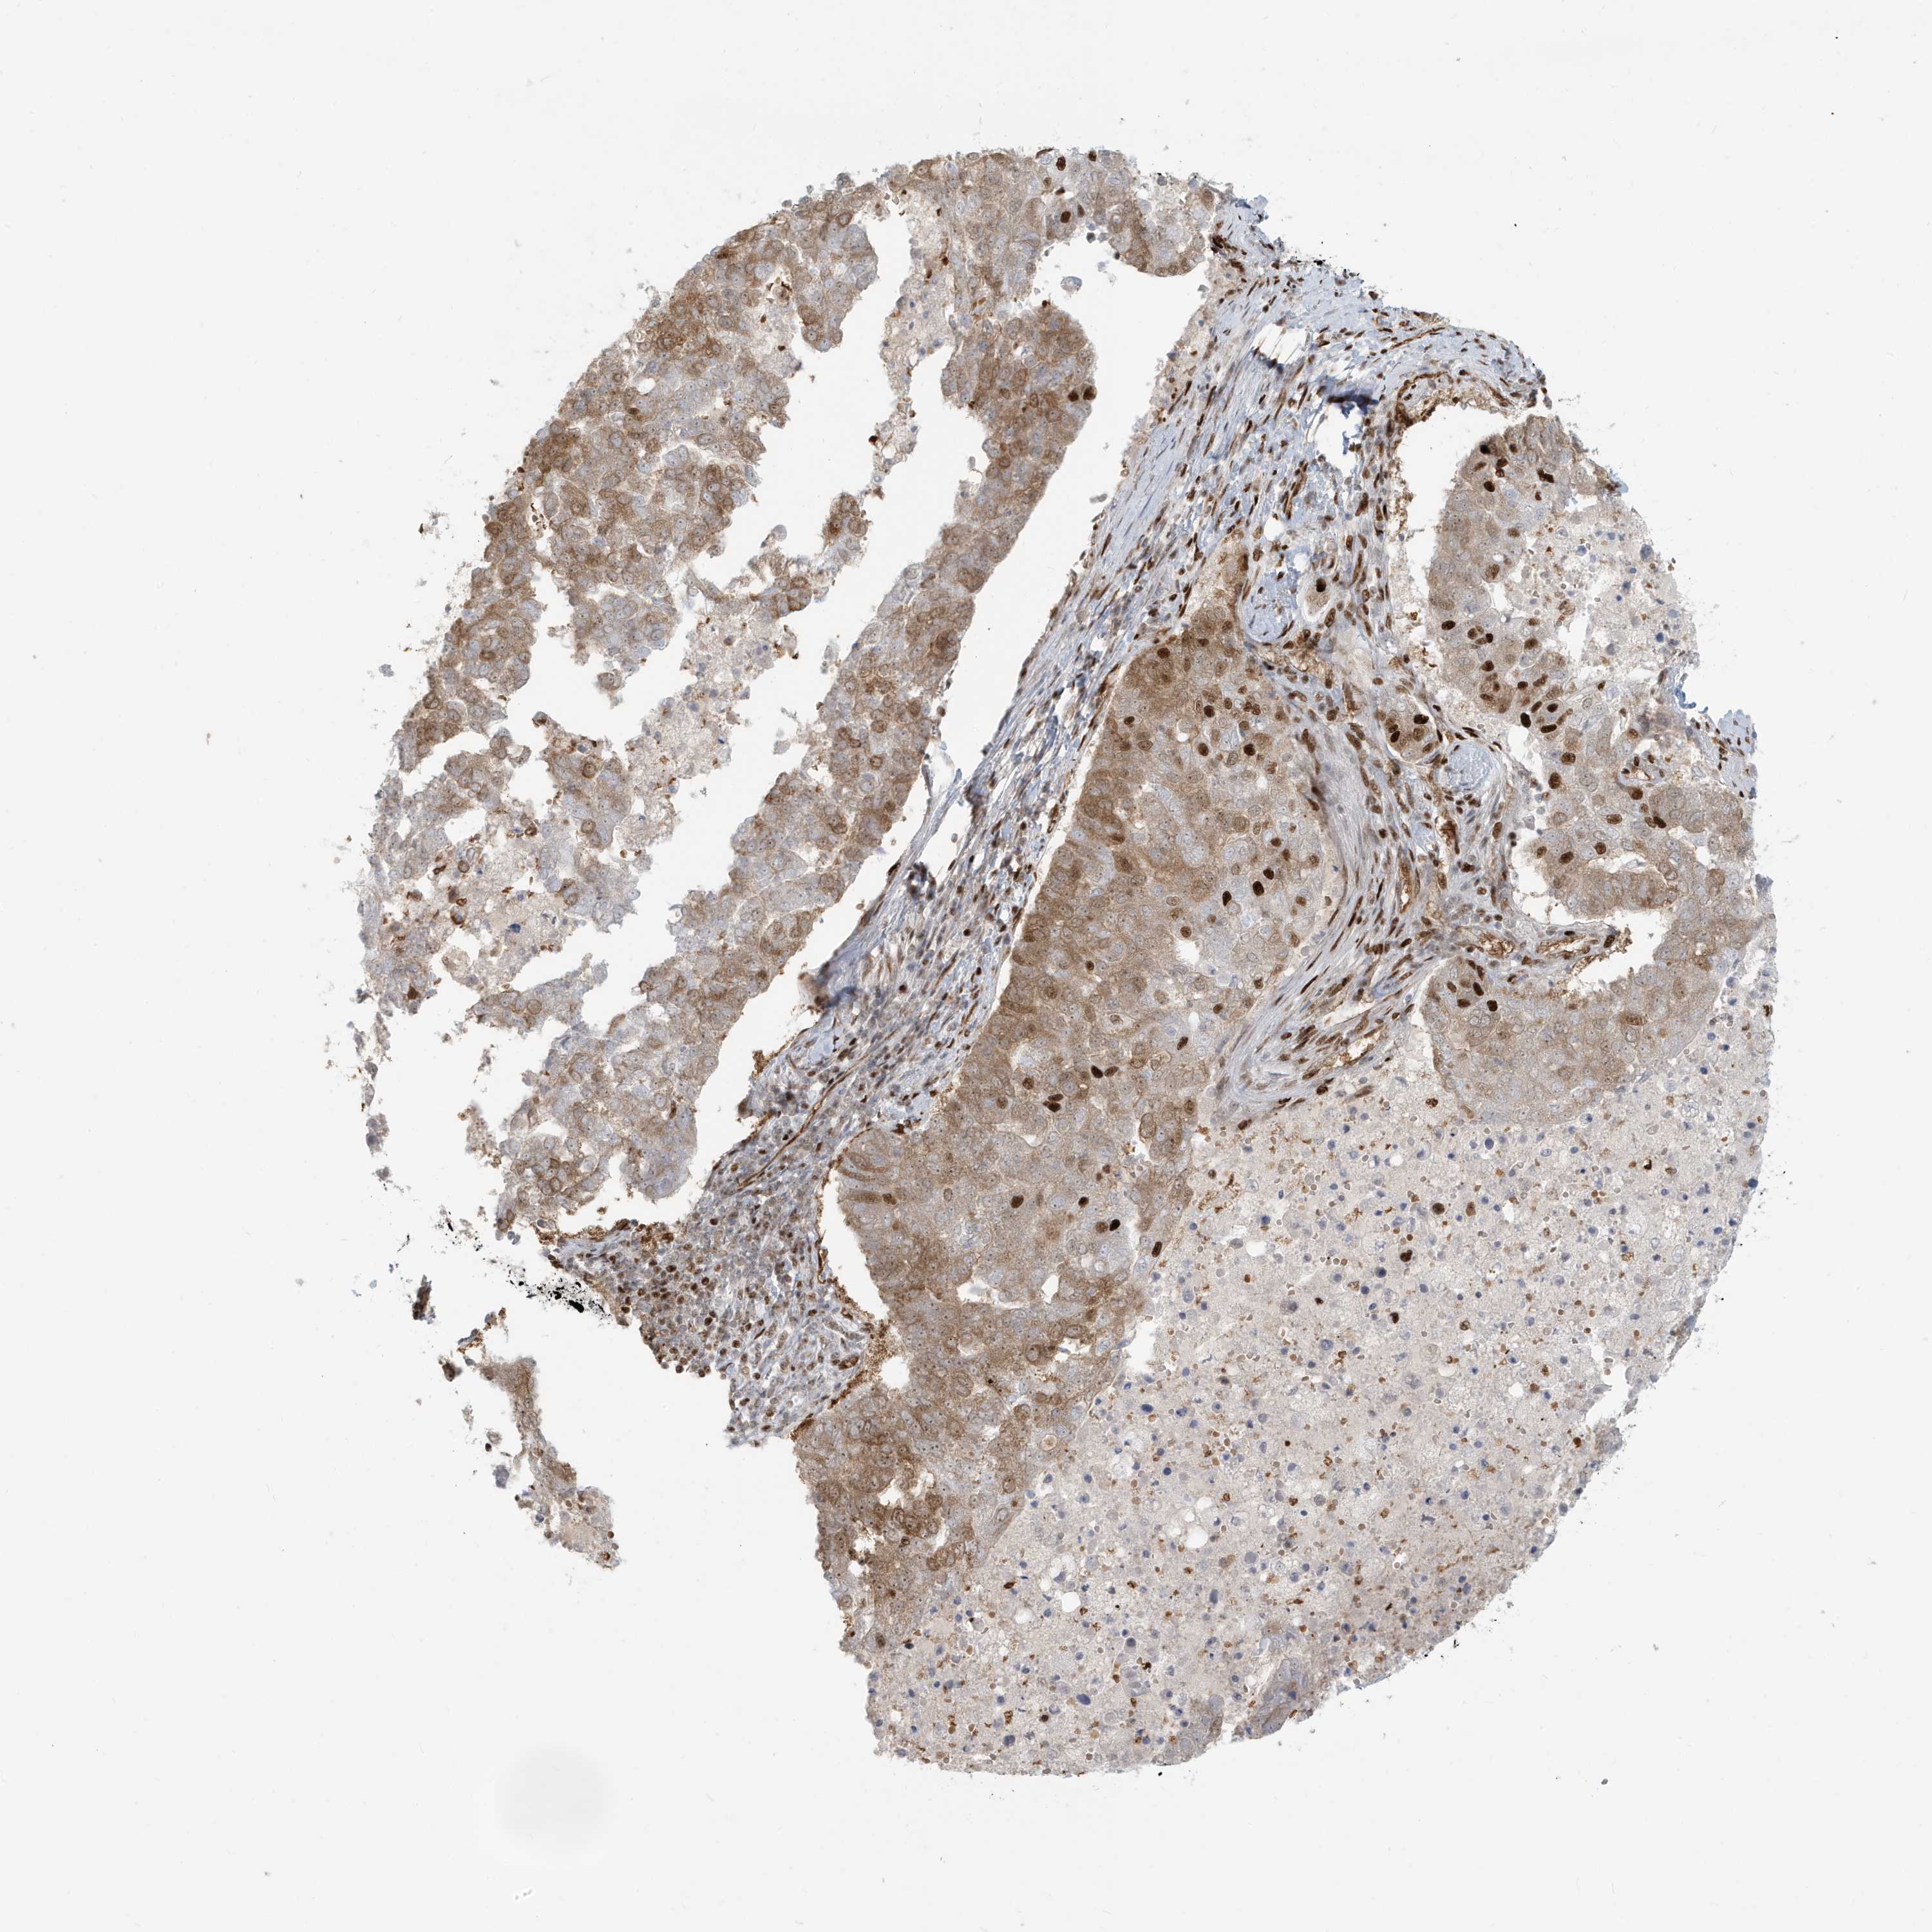

PANCREATIC CANCER - Protein expressioni

A mouse-over function shows sample information and annotation data. Click on an image to view it in a full screen mode. Samples can be filtered based on level of antibody staining by selecting one or several of the following categories: high, medium, low and not detected. The assay and annotation is described here.

Note that samples used for immunohistochemistry by the Human Protein Atlas do not correspond to samples in the TCGA dataset.

Antibody stainingi

Antibody staining in the annotated cell types in the current human tissue is reported as not detected, low, medium, or high, based on conventional immunohistochemistry profiling in selected tissues. This score is based on the combination of the staining intensity and fraction of stained cells.

Each image is clickable and will lead to virtual microscopy that enables deeper exploration of all samples and also displays staining intensity scores, fraction scores and subcellular localization as well as patient and tissue information for each sample.

Antibody HPA030762

Staining

High

Medium

Low

Not detected

Intensity

Strong

Moderate

Weak

Negative

Quantity

>75%

75%-25%

<25%

None

Location

Nuclear

Cytoplasmic/membranous

Cytoplasmic/membranous,nuclear

Adenocarcinoma, NOS